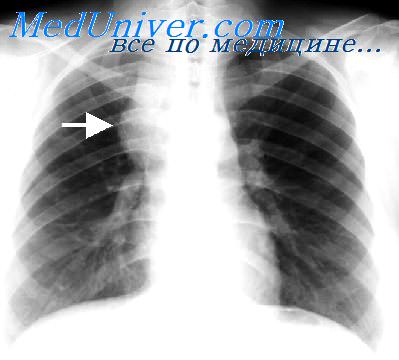

Рентгеновские снимки тератомы средостения: Диагностика и лечение

Раздел: Фотоэссе